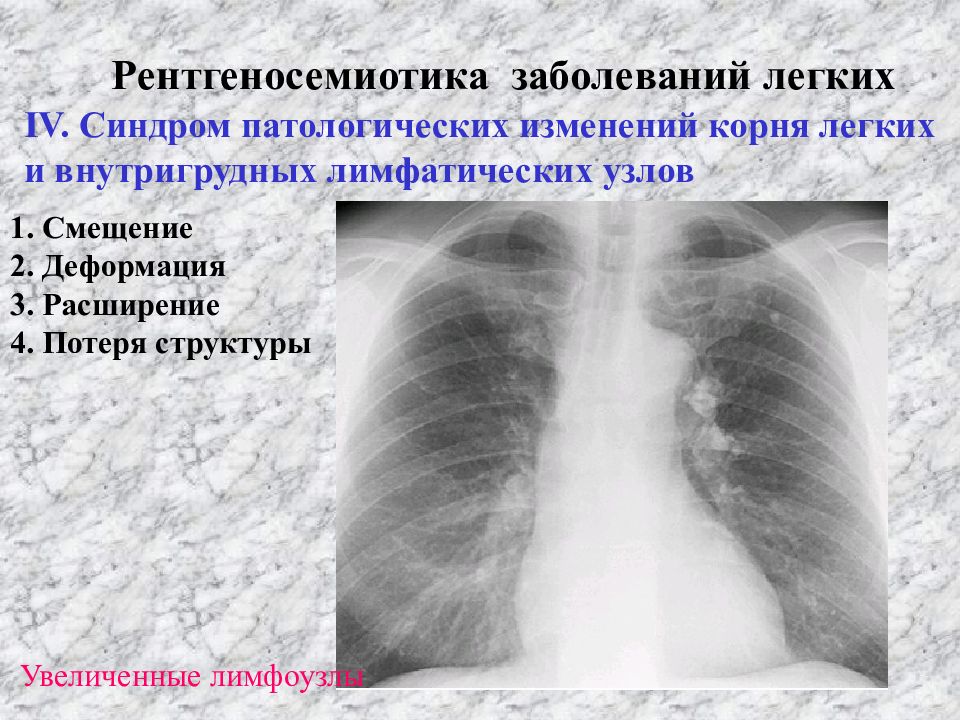

Рентгенологические изображения и синдромы патологии легких

Раздел: Кадры-подсказки